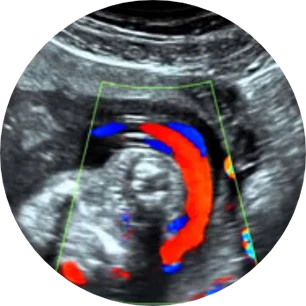

FLUJOMETRÍA O ULTRASONIDO DOPPLER

La flujometría o ultrasonido Doppler es un estudio prenatal no invasivo que sirve en todos los trimestres del embarazo, en especial para el tercer trimestre. Por medio de la valoración de las arterias uterinas, cerebral media y arteria umbilical, puede confirmarse si la circulación materno fetal es adecuada;

Alteraciones a nivel placentario (arterias uterinas, arteria umbilical), a nivel cerebral fetal (arteria cerebral media) o a nivel cardiaco fetal (ductus venoso, istmo aórtico). - Mi médico encontró una alteración con la flujometría o ultrasonido Doppler ¿qué sigue? ¿qué hacer?